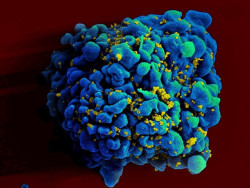

La terapia antirretroviral inmediata hace 100 veces más pequeños los reservorios de VIH en humanos

Un equipo internacional de investigadores del Centro de Investigación Hospitalaria de la Universidad de Montreal (CRCHUM), el Programa de Investigación Militar sobre el VIH de los Estados Unidos y el Centro de Investigación sobre el SIDA de la Cruz Roja Tailandesa ha demostrado que los primeros reservorios de VIH establecidos siguen siendo "sensibles" durante estas etapas tempranas y podrían reducirse unas 100 veces al iniciarse inmediatamente el tratamiento antirretroviral.